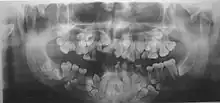

• The permanent teeth include supernumerary teeth. Unless these supernumeraries are removed they will crowd the adult teeth in what already may be an underdeveloped jaw. If so, the supernumeraries will probably need to be removed to make space for the adult teeth. Up to 13 supernumerary teeth have been observed. Teeth may also be displaced. Cementum formation may be deficient.[13]

• Failure of eruption of permanent teeth.

Different features of the dysostosis are significant. Radiological imaging helps confirm the diagnosis. During gestation (pregnancy), clavicular size can be calculated using available nomograms. Wormian bones can sometimes be observed in the skull.[19]

Diagnosis of CCD spectrum disorder is established in an individual with typical clinical and radiographic findings and/or by the identification of a heterozygous pathogenic variant in RUNX2 (CBFA1).[20]